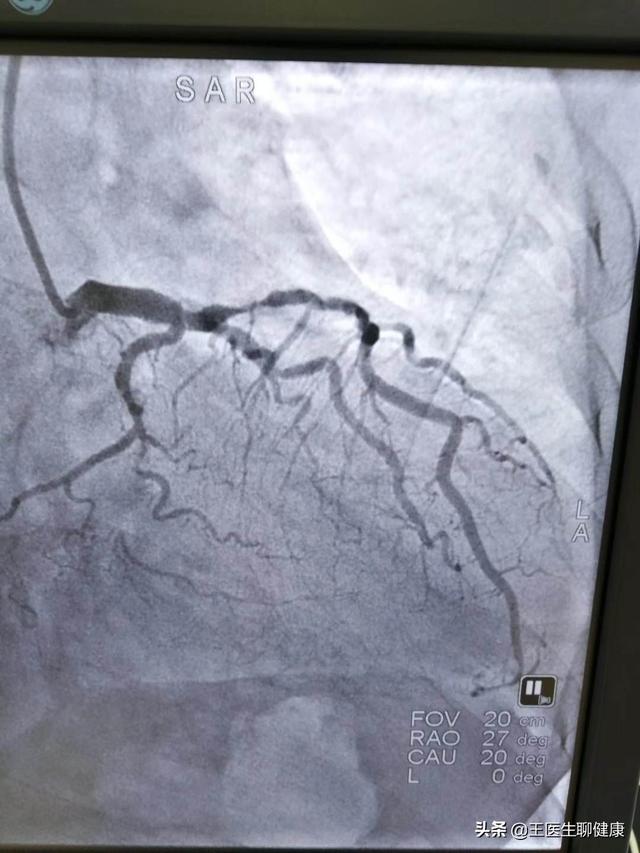

4、石灰化を伴う多枝病変:冠動脈造影の結果、左主幹+3枝病変を含む冠動脈の多枝病変が認められ、ステント治療が可能であるが、多くのステントを留置する可能性があり、石灰化病変は手術が難しく、手術時間が長く、大量の放射線が必要である。外科的バイパス手術も考えられるが、バイパス手術は回復が遅く、治療期間も長い。状況に応じて、医師が理想的なプランを提示します。

下図は左主幹部の多枝病変である。